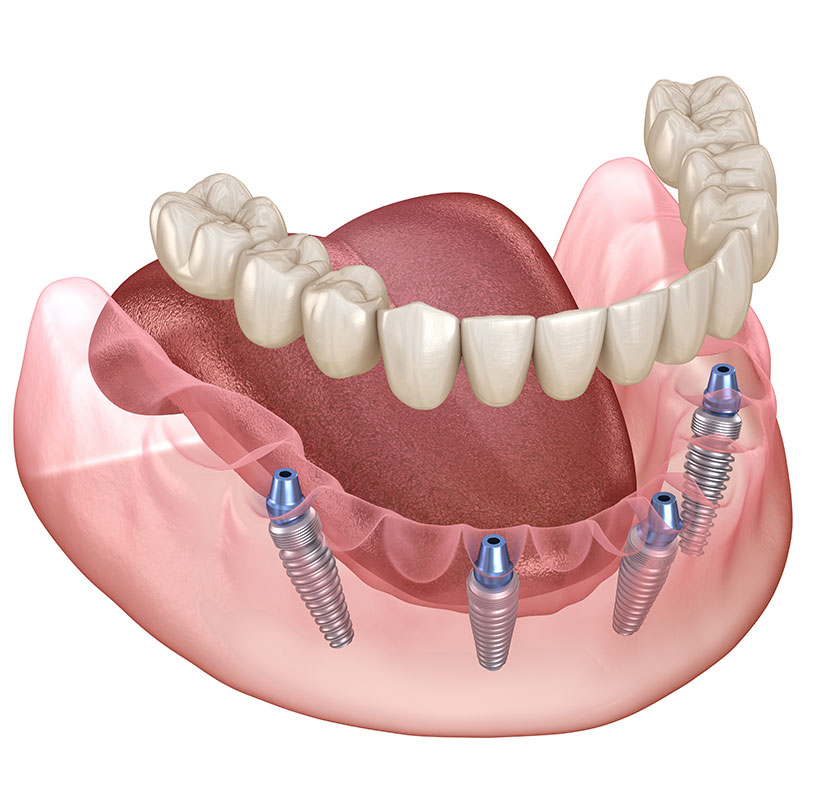

歯を失ってしまった場合、欠損部に人工歯根と人工歯を取り付け、機能性と審美性を回復させる治療です。豊富な治療経験と高い技術力をいかし、1本欠損から全部欠損まで、骨の少ない場合も含めて、要求の高い複雑なケースにも対応しています。痛みや腫れの少ない低侵襲インプラント治療のご提供を心がけています。

科学的根拠に基づいた的確な診査・診断と治療プラニング、高度な外科手技と合わせ、安全と信頼性に優れたインプラントシステムを導入し、高い成功率と満足を目指しています。